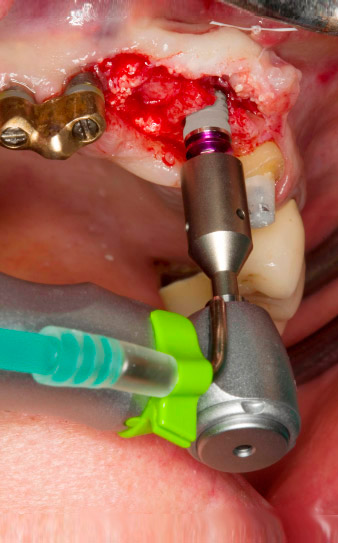

Following primary healing, the soft tissues were shaped using the basally lined bridge. Two months later the site was exposed by a slightly palatal alveolar ridge incision (Fig 2). The dimensions of the alveolar bone proved to be sufficient at position 22. Figures 2 and 4 show the preparation of the implant bed, the tapping and the implantation using Implantmed.

The new implantology motor was used with the appropriate W&H surgical contra-angle handpieces.

In order to compensate for the periodontal bone loss and achieve an aesthetically pleasing result, the implantation was combined with guided bone regeneration (GBR) with xenogenic replacement material and a collagen membrane

(Fig. 5 and 6).